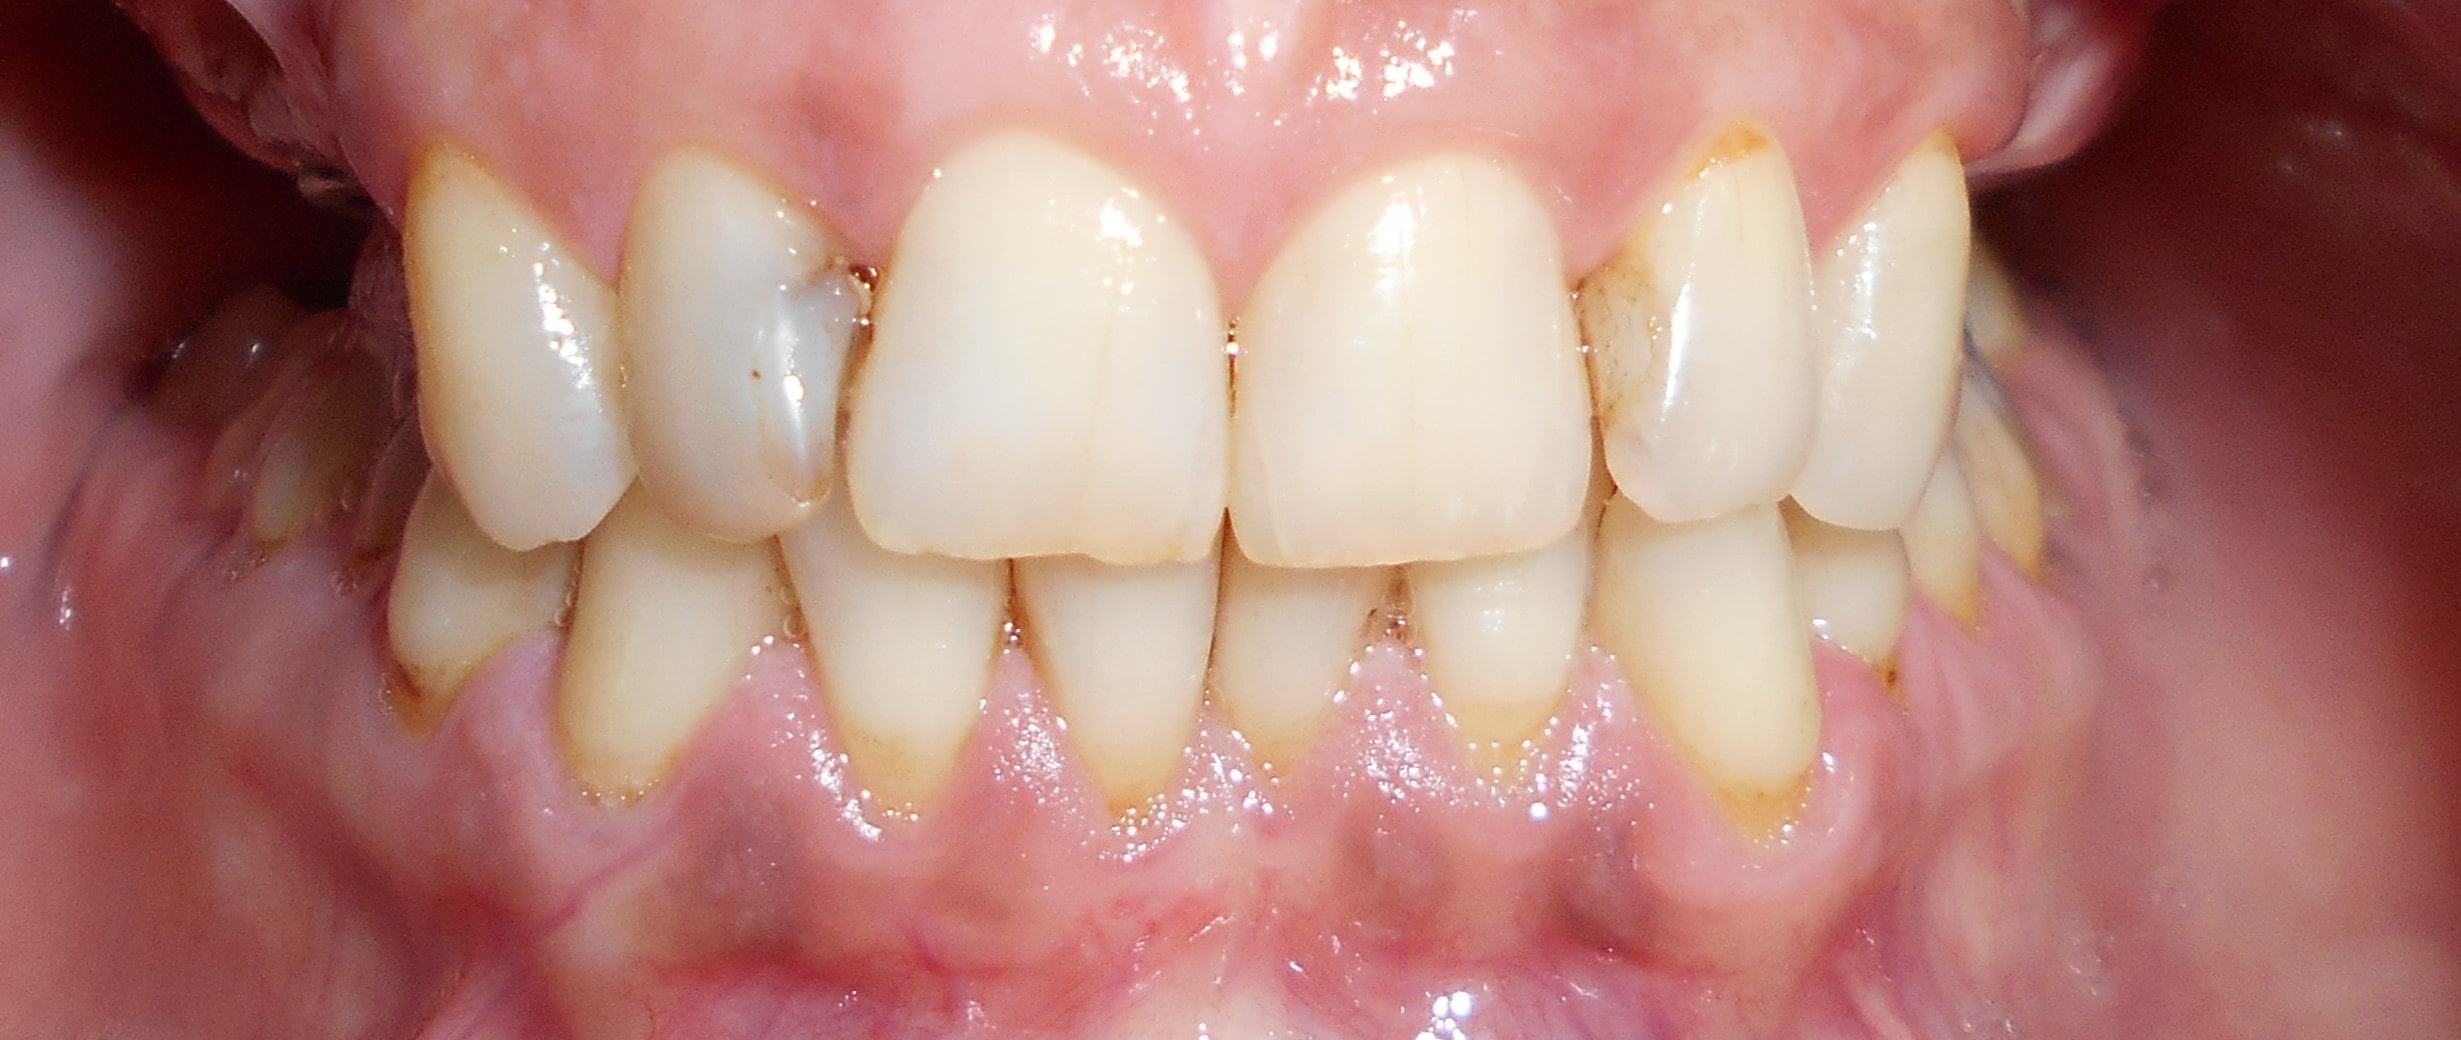

Pacijent iz Nemačke, kod koga smo estetsko i funkcionalno zbrinjavanje rešili cirkonijum keramičkim krunicama sa ugradnjom kratkih implantata u donjoj vilici zbog smanjene visine kosti, a u gornjoj vilici na levoj strani odmah nakon vađenja zuba je ugrađen standardni implantata na mesto izvađenog zuba i ugrađen je tuberopterigoidni implantat da se ne bi radila komplikovana sinus lift procedura koja bi produžila vreme završetka rada na godinu i više dana. Rad uspešno završen i pacijent nema nikakvih problema već pet godina.

Pacijent sa obe strane gornje vilice je bio bezub, sa minimalnom horizonatlnom i vertikalnom visinom kosti kao i sa spuštenim sinusom. Nakon dužeg traženja rešenja za svoj slučaj u drugim ordinacijama da bi izbegao komplikovanu sinus lift proceduru prihvatio je naš predlog da se ugrade po tri implantata sa obe strane gornje vilice od kojih su dva tuperopterigoidna implanta, koji su rešili problem spuštenog sinuasa sa minimalnom traumom prilikom ugradnje. Slučaj rađen pre četiri godine. Na poslednjoj kontroli izgleda besprekorno.

Pacijent kod koga je rađena kombinacija rešavanja bezubih prostora sa ugradnjom implantata, a nakon tri meseca kompletno rešavanje sa cirkonijum keramičkim -bezmetalnim krunica i mostovima.